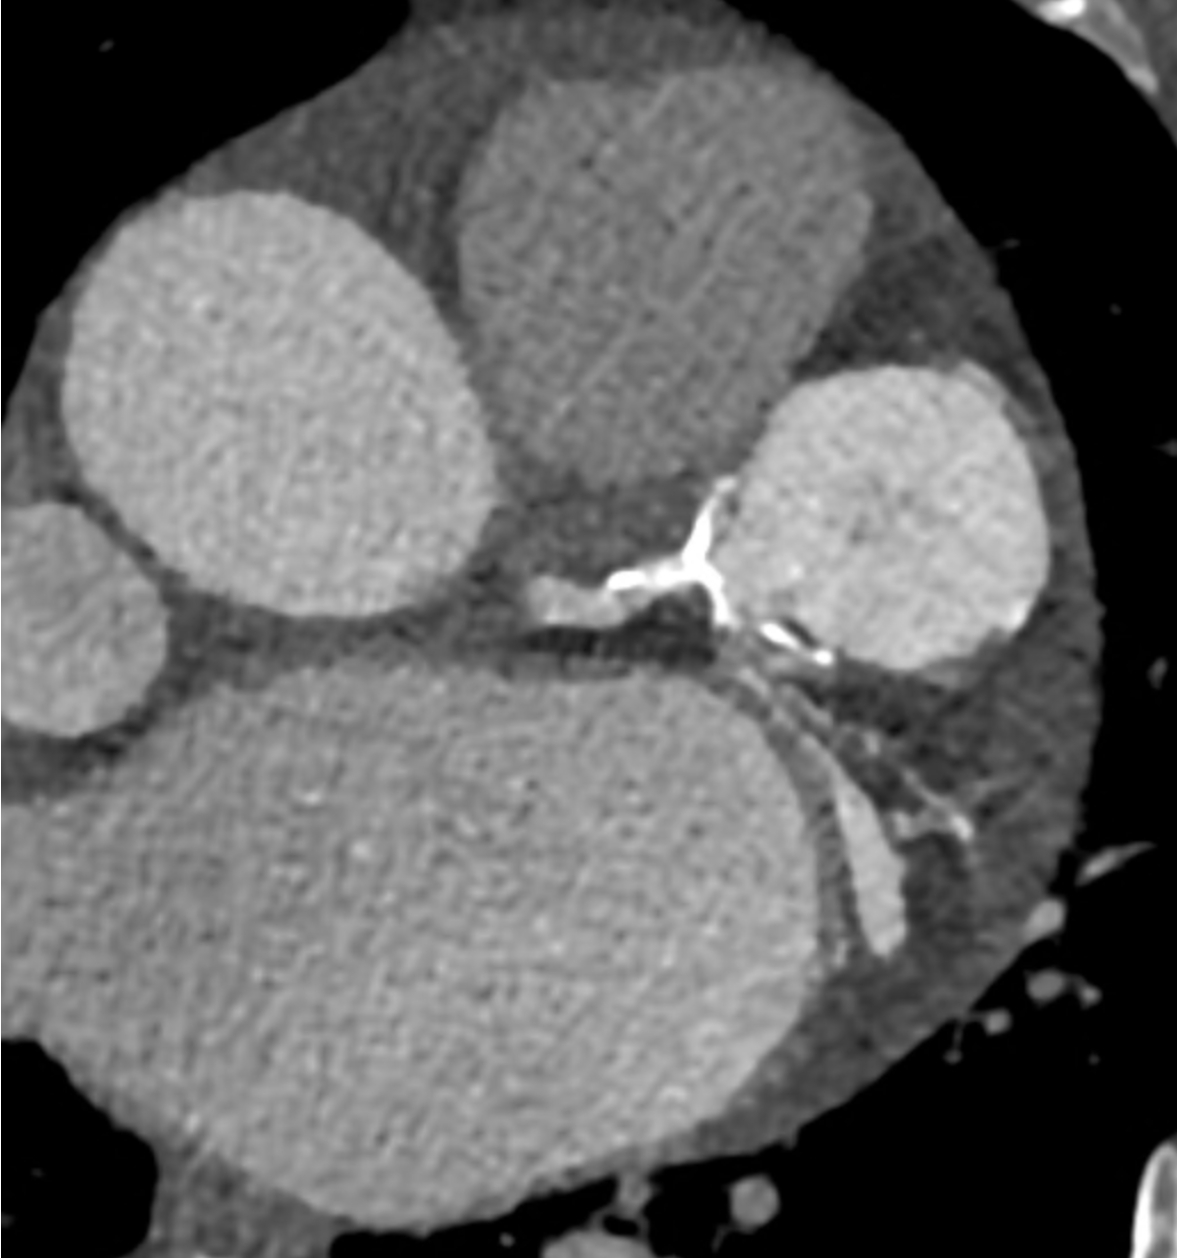

A 78-year female with a history of hypertension, hyperlipidemia, HIV, and rheumatoid arthritis presented with atypical chest pain. Coronary CTA was performed, revealing an incidental calcified saccular aneurysm, with a size of 33.9 x 33.4 mm, arising from the distal LMCA with intra-aneurysmal calcifications and thrombus (Figure 1). The aneurysm caused mild luminal compression of the proximal LAD (p-LAD). Coronary arteries were non-obstructive. Invasive coronary angiogram was done and the patient underwent coiling embolization to exclude the aneurysm with no periprocedural complications (Figure 2). The patient tolerated the procedure and is planned to have both clinical and non-invasive imaging follow-up. In this patient, CTA enabled prompt diagnosis and guided further intervention.